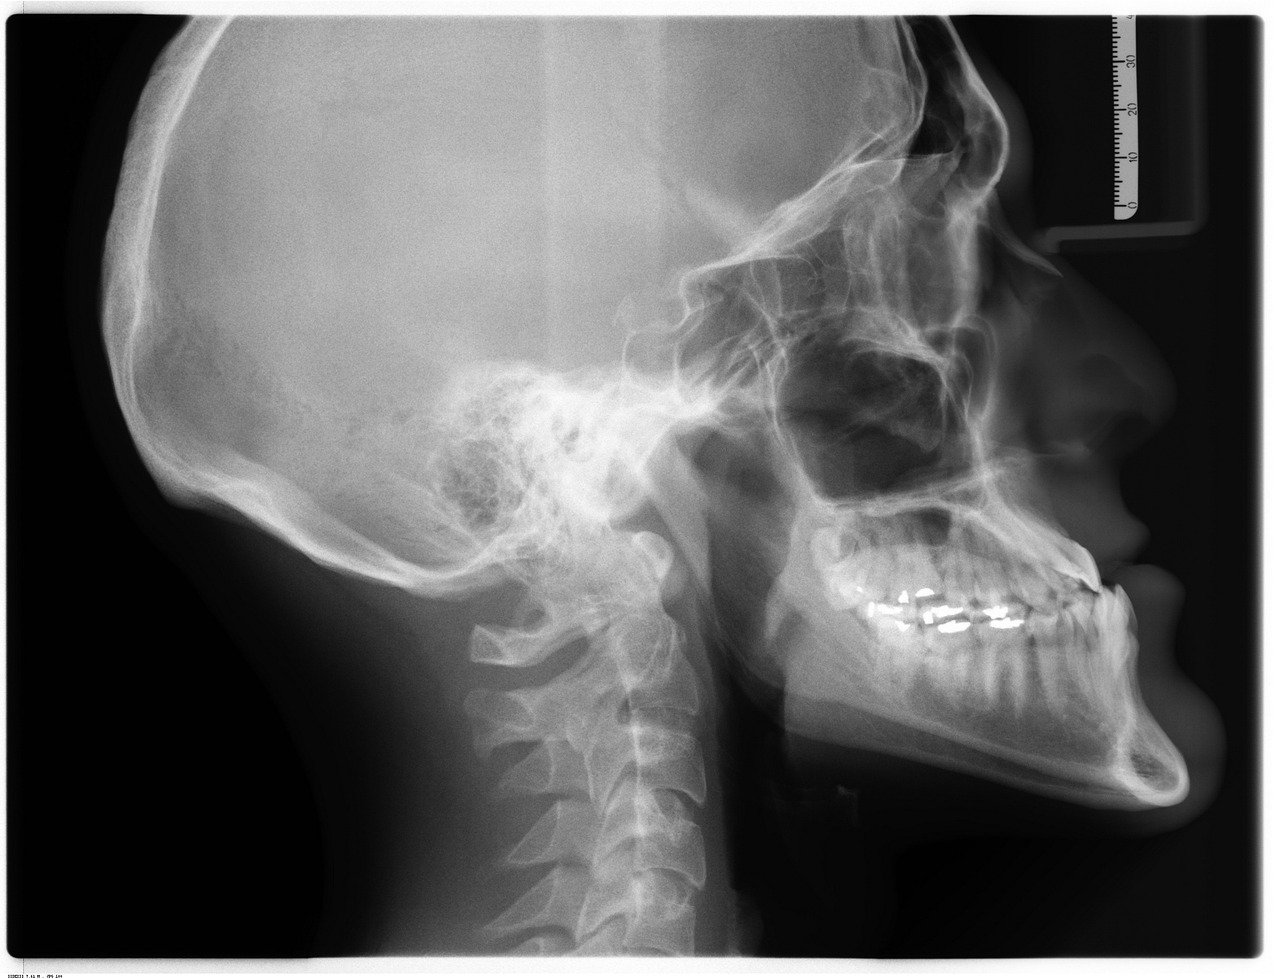

The three-dimensional aspect also revolutionizes orthodontic diagnosis and treatment planning. CBCT provides detailed information about tooth root positions, bone thickness, and anatomical limitations that influence tooth movement. Orthodontists can visualize the entire dentofacial complex and plan treatments with greater precision, especially for complex cases involving impacted teeth or skeletal discrepancies.

Orthognathic surgery planning represents another area where CBCT’s real-time cross-sectional views provide substantial advantages. Surgeons can evaluate skeletal relationships, measure bone dimensions, and plan osteotomy locations with unprecedented accuracy. The ability to visualize hard and soft tissue relationships in three dimensions during the planning session improves surgical outcomes and reduces operative time.

Orthodontic treatment planning relies heavily on conventional radiographs for initial assessment and progress monitoring. Panoramic radiographs provide comprehensive views of tooth development, eruption patterns, and potential impactions. Cephalometric radiographs offer standardized measurements for growth assessment and treatment planning in orthodontic cases.